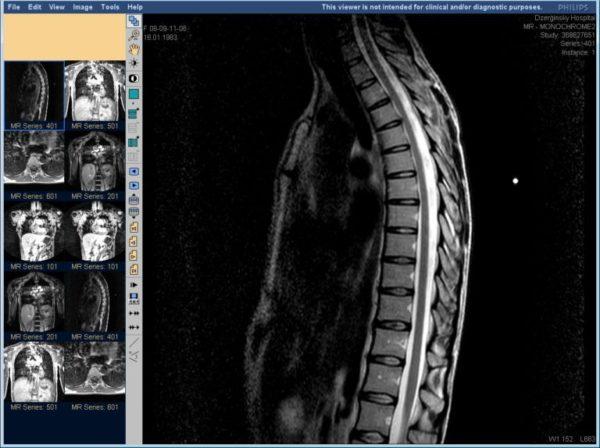

- УЗИ грудного отдела позвоночника проводится только новорожденным детям. Поскольку, взрослые в этом отделе имеют достаточно узкие промежутки между самими позвонками. Поэтому, в этом случае УЗИ-диагностика просто невозможна. И как раз здесь лучше назначить исследование методом МРТ.

Что лучше: УЗИ позвоночника или МРТ

Пациенты, желающие пройти обследование позвоночника, иногда теряются в выборе: проводить его методом МРТ или УЗИ. МРТ – это компьютерное обследование, которое основано на применении магнитного резонанса соединений атомов, входящих в состав человеческих тканей.

Зачастую, УЗИ назначают в комплексе с проведением другого метода исследования, такого как МРТ. Цель проведения данных процедур – одна, но сами они имеют существенные отличия. Но, можно ли сделать только УЗИ позвоночника, без применения МРТ?

Но, для справедливости стоит отметить, что ультразвуковой метод не выявит наличие межпозвоночных грыж крестцовой области позвоночника. А вот магнитно-резонансная томография хорошо определит выпадение межпозвоночных дисков.

Но для исследования на наличие всех остальных патологий позвоночного столба, о которых мы сегодня уже говорили, и причин их образования, вполне достаточно применения одной лишь современной методики УЗИ. Поэтому не всегда целесообразно переплачивать ещё и за проведение МРТ.